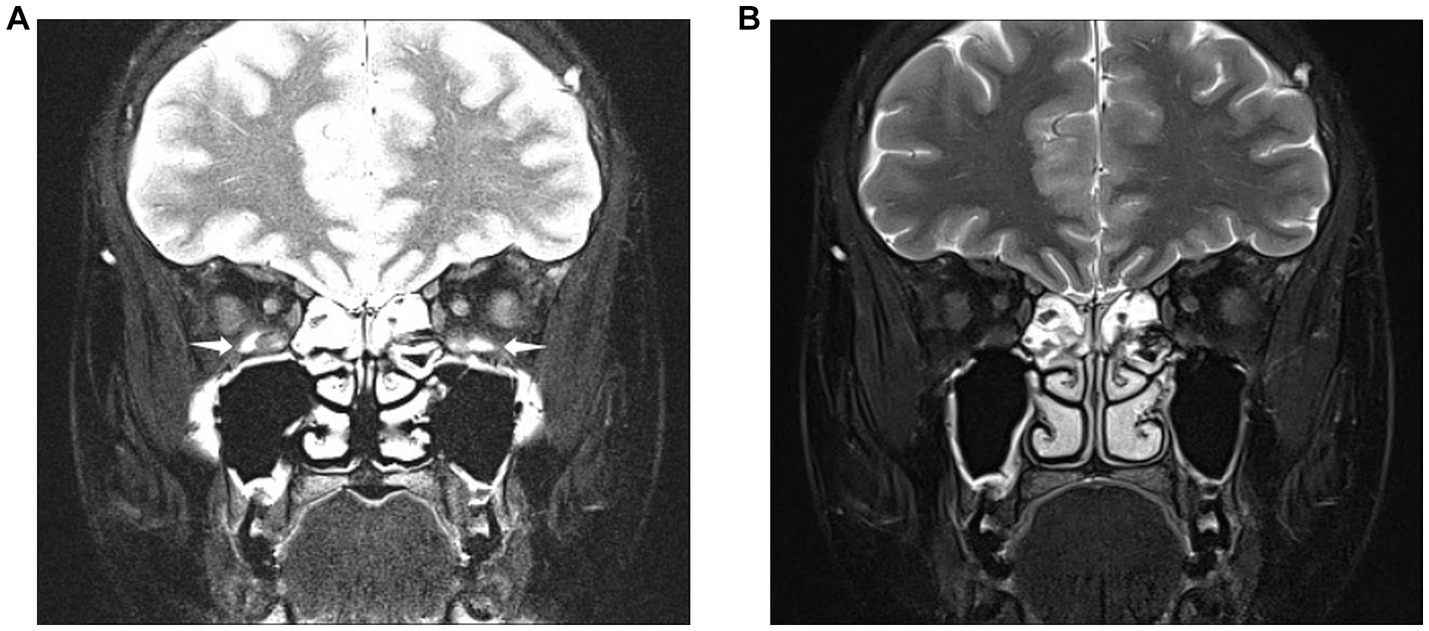

Figure 2. Images obtained from a 28-year-old woman diagnosed with thyroid eye disease. Coronal SPAIR-transverse relaxation (T2)-weighted imaging (T2WI) (A) and water-only Dixon-T2WI (B). The latter image shows a more uniform fat suppression on the orbit and periorbital tissue than the former. Coronal SPAIR-T2WI (A) displaying the major susceptibility artifacts (white arrowheads) involving both inferior rectus muscles, hindering accurate analysis of muscular signal. Coronal water-only Dixon-T2WI (B) displaying the fewer susceptibility artifacts and strong fat-suppression ability.

The coronal water-only Dixon-T2WI and SPAIR-T2WI data of each eye were analyzed. All parameters were measured using the Picture Archiving and Communication Systems of the Shunde Hospital of Southern Medical University (Yi Lianzhong Ruitu, Version 3.7, Guangzhou, Guangdong, China). Two radiologists analyzed the images independently by using the blind method and resolved disagreements through consultations. In our study, the subjective evaluation of image quality such as FS quality and artifacts of Dixon-T2WI and SPAIR-T2WI is conducted concurrently by radiologists (Figure 2).